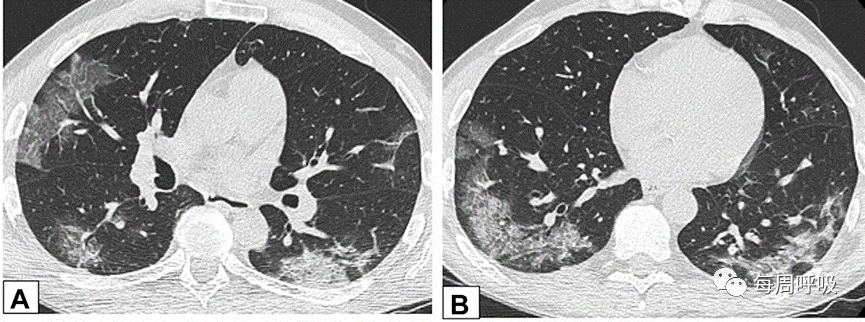

图3 支气管血管束分布 在活检证实的机化性肺炎患者中,通过中(A)和下(B)肺区的轴位增强CT扫描图像显示双侧多灶性支气管血管周围实变灶。